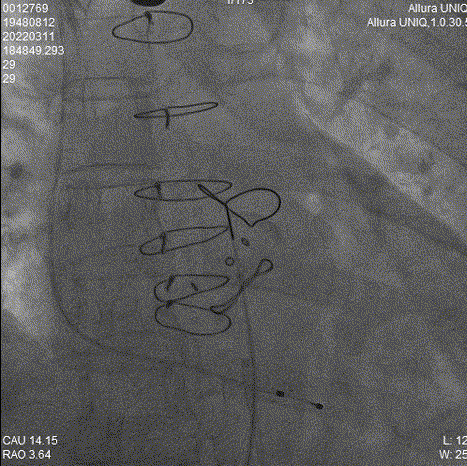

瓣膜释放过程